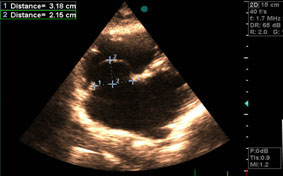

UW MEDICINE | PATIENT EDUCATION _____ _____ Page 1 of 7 | Atrial Fibrillation Regional Heart Center | Box 356161 1959 N.E. Pacific St ., Seattle, WA 98195 | 206-598-4300 . Atrial . This handout describes atrial fibrillatio n  This test uses ultrasound waves to make images of your heart  ... Fetch Content